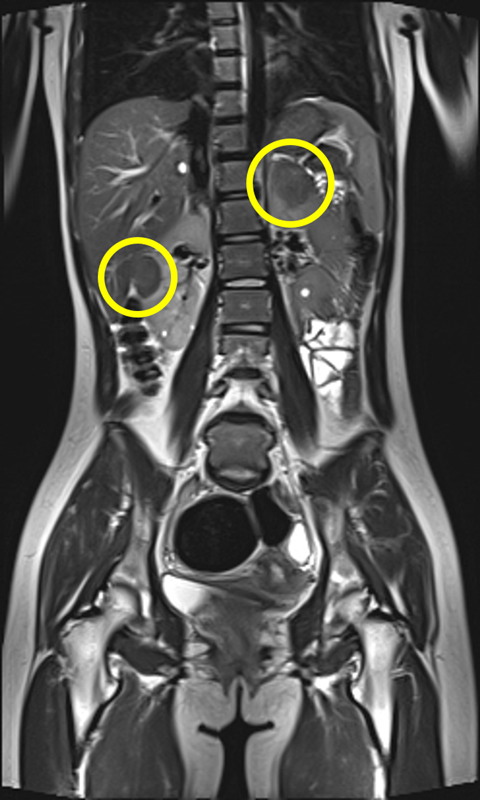

결절 경화증(tuberous sclerosis complex, TSC)은 종양억제유전자의 돌연변이로 인해 세포 증식이 조절되지 않고, 뇌·신장·피부·심장·폐 등 여러 장기에서 양성 종양이 발생하는 유전 희귀질환이다.

가장 흔한 증상인 뇌전증 발작과 피부의 혈관섬유종, 백반증을 비롯해 자폐스펙트럼장애, 인지장애, 신장 낭종, 폐세포 증식증 등 다양한 증상이 연령과 상관없이 나타나기 때문에 조기 진단과 장기적 관리가 필수적이다.